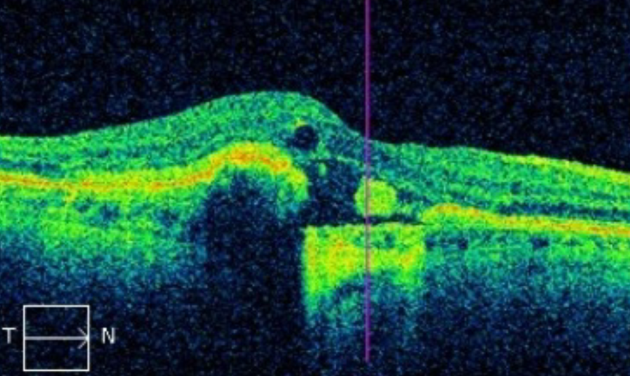

Рисунок » Макулярное отверстие»